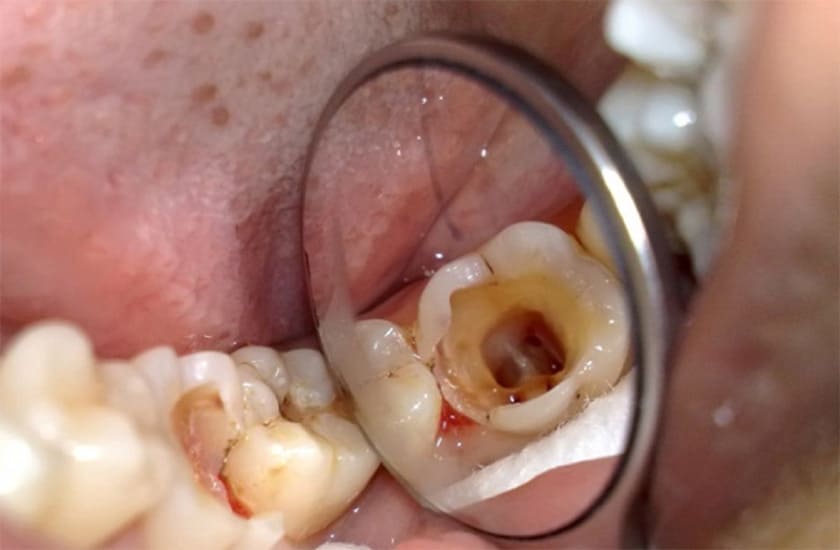

Răng sâu lỗ to là tình trạng sâu răng ở giai đoạn nặng, khi vi khuẩn đã tấn công và phá hủy một phần lớn cấu trúc răng. Khi đó, bạn sẽ quan sát thấy các lỗ sâu rõ ràng trên bề mặt răng, thậm chí có thể lớn đến mức khiến răng bị vỡ hoặc mẻ.

Nếu không được điều trị kịp thời, răng sâu lỗ to sẽ dẫn đến nhiều biến chứng như viêm tủy răng, áp xe răng, và thậm chí là mất răng. Do đó, khi phát hiện tình trạng răng sâu lỗ to, bạn cần tìm đến nha sĩ để được thăm khám và điều trị phù hợp.

Trong trường hợp răng sâu lỗ to mức độ nặng, tổn thương đã lan rộng, ăn mòn phần lớn cấu trúc răng, khi đó, trám răng sẽ không hiệu quả. Thay vào đó, bác sĩ sẽ tiến hành điều trị tủy răng và phục hình thân răng bằng các biện pháp như trám bít kênh tuỷ, đặt chốt cùi, bọc mão sứ…

Nếu tình trạng răng sâu lỗ to không được điều trị kịp thời, vi khuẩn có thể xâm nhập vào tủy răng, gây viêm, nhiễm trùng tủy. Khi đó, bạn sẽ cảm thấy răng nhạy cảm, ê buốt hoặc đau nhức dữ dội. Răng sâu lỗ to lan đến tủy sẽ cần được điều trị tủy trước khi tiến hành trám răng hoặc phục hình.